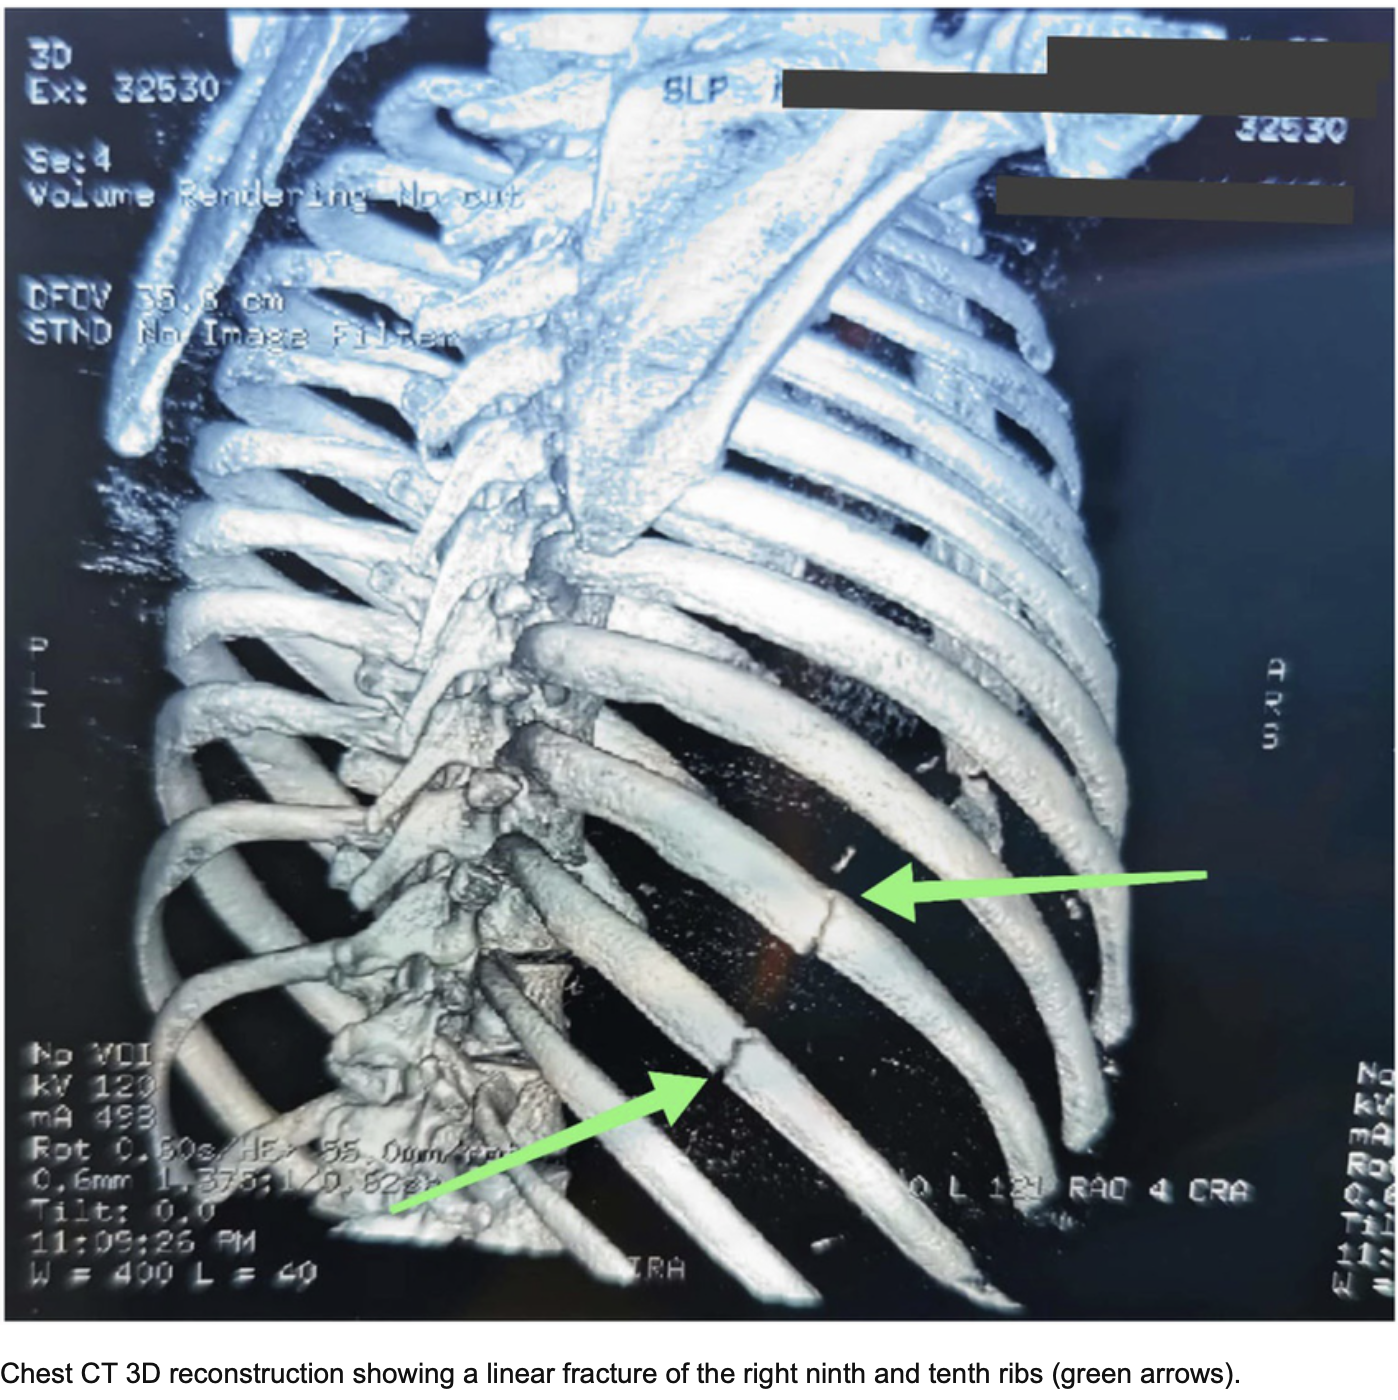

骨折した部位が明瞭に描出されています.

引用元:Alhatemi AQM. Rib fracture secondary to cough‐induced trauma. Clin Case Rep. 2024. 12.

11時半すぎに救急車が到着しました. 頬と胸をぶつけたようでした. 特にほほの骨(頬骨きょうこつ)と9, 10, 11番目の肋骨を圧すと痛みが強いので, 骨折を疑って頭と胸のCTを撮像するようにオーダーしました. CTを確認しましたが, 頬骨に骨折はありませんでした. また, 肋骨にも骨折はありませんでした.

肋骨は弯曲しているので, 骨折部にズレがない骨折だと, X線写真の角度によっては骨折が写らないことがあります. 骨折を見逃さないようにするためには, CTを撮像して, 3−D再構築画像として確認する必要があります. 特に, 交通事故や労災事故では, 骨折を見逃すと, 後々問題となるので, 必ずCTを撮像することにしています.